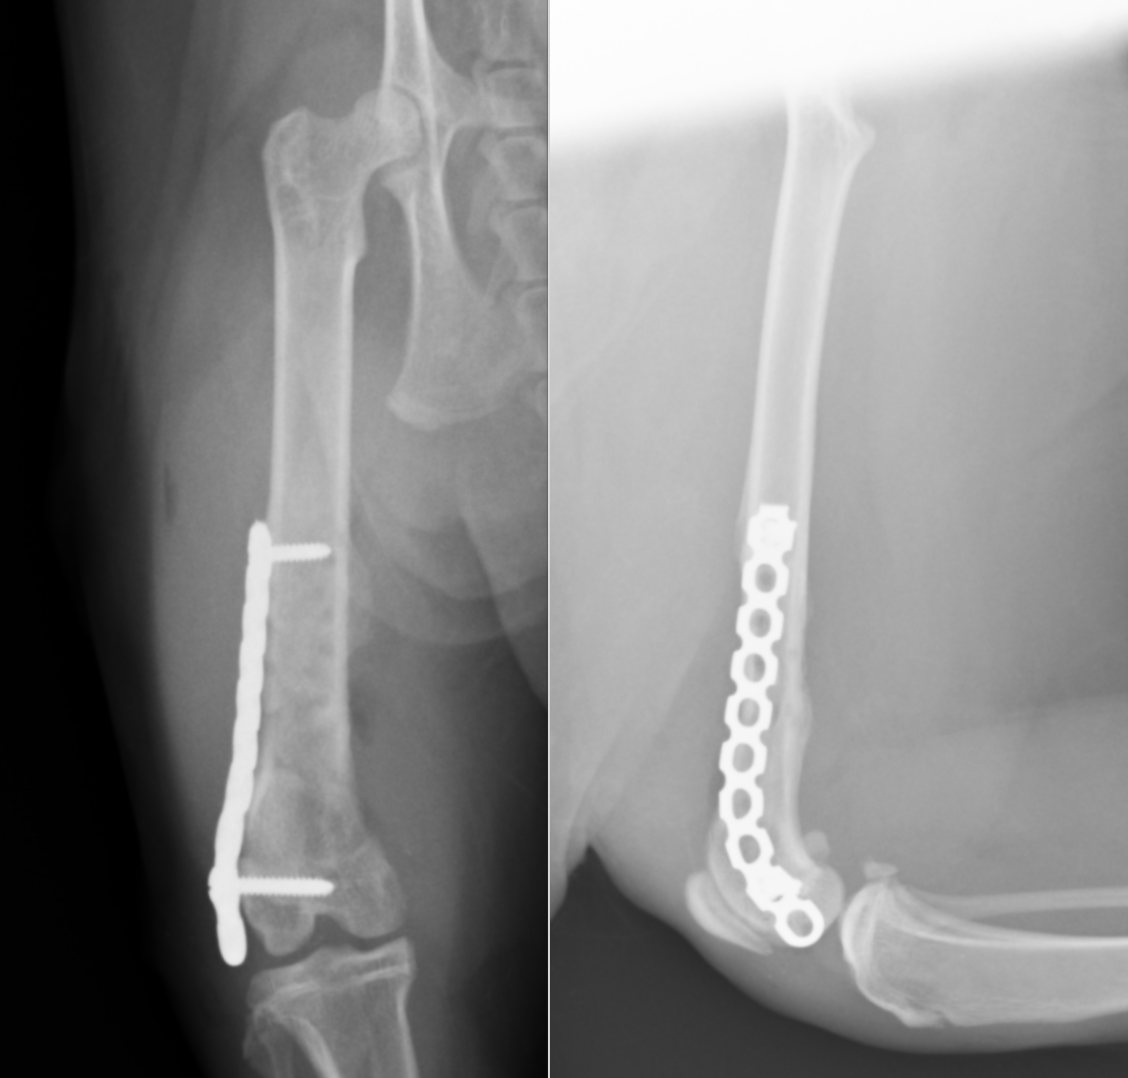

治療は手術による固定が必要で、骨折線近くにはインプラントの挿入は困難であると予想されたため、まず最初に長さを維持する髄内ピンを挿入しました(長いピン)。それによりある程度の位置は合ったため、その状態で、外側にプレートを設置しました。外側には2本しかスクリューを入れられなかったため、ロッキングスクリューを入れ固定しました。その状態で、内側の骨片に欠損が見られたため(おそらく欠けた骨)、内側にも補助的にプレートを設置しました。

術後のレントゲンです。髄内ピンとして長いピンが2本と、外側にLCPというプレートと、ロッキングスクリュー、内側にリコンストラクションプレートと、コーテックススクリューが設置されています。